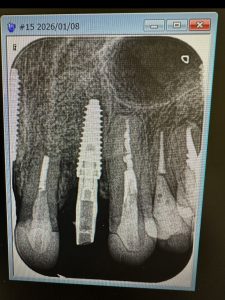

画像は全てメタルプレート、クリアランスが少ない

オペ後6から7wでの22番インプラント印象

ISQ75全周

これで6本目

ナイトガード干渉なく、奥🟦が消えるまで